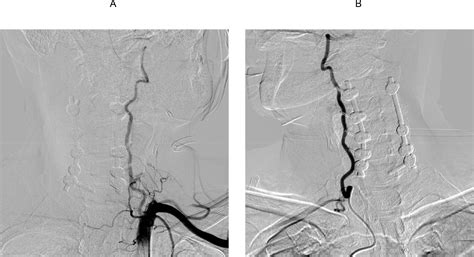

• Digital Subtraction Angiography (DSA): Considered the "gold standard," this invasive procedure involves injecting contrast dye to map the arteries with high resolution.

3. Endovascular Stenting: A minimally invasive procedure where a small mesh tube is placed inside the artery to hold it open and restore blood flow.